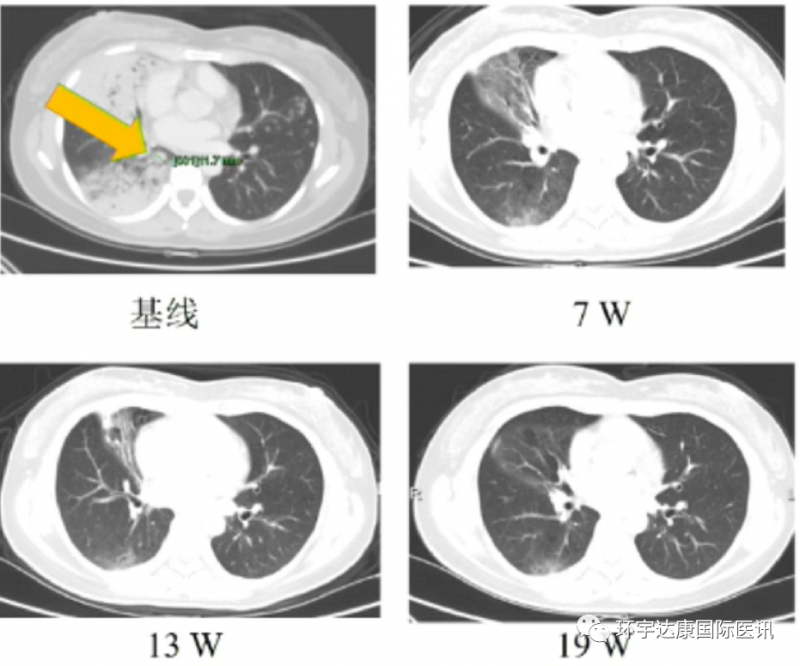

一位38岁的女性确诊为ROS1阳性非小细胞肺癌,既往接受过化疗及克唑替尼治疗失败,并产生ROS1 G2032R耐药突变。接受Taletrectinib治疗后7周,靶病灶缩小30%以上,治疗13周后,靶病灶完全消失。接受治疗时间近7个月。